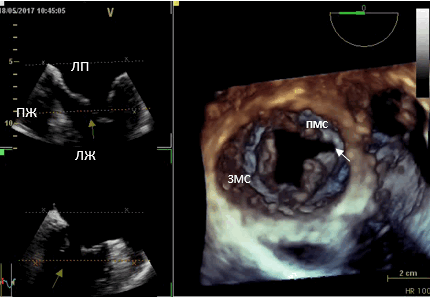

Трёхмерная чреспищеводная эхокардиография (3D-ЧП ЭхоКГ) по сравнению с двухмерной позволяет получить наиболее полное представление о морфометрии отдельных структур и сердца в целом. Методика интраоперационной 3D ЧП ЭхоКГ незаменима при выполнении реконструктивных вмешательств у пациентов с митральной недостаточностью (МН), которая занимает второе место в структуре пороков сердца. Согласно рекомендациям Европейского общества кардиологов (ESC) и Европейской ассоциации кардиоторакальных хирургов (EACTS) 2017 года, именно реконструктивные операции на митральном клапане у пациентов с недостаточностью приобретают приоритетное значение. Безусловными преимуществами пластических операций являются низкий риск развития тромбоэмболий и эндокардита, лучшая отдалённая выживаемость и свобода от приёма антикоагулянтов. Успех хирургического лечения с использованием реконструктивного подхода во многом зависит от уровня и качества выполненных диагностических исследований.

Трёхмерная интраоперационная чреспищеводная эхокардиография позволяет в режиме реального времени проводить построение модели клапана, которая максимально сопоставима с видом клапана, каким его видит хирург в операционном поле («surgical view»), и детально оценить его анатомию, геометрию и функцию. На основании полученных данных хирург имеет объективную возможность определить тактику операции, объём и вид реконструкции клапана. После выполненной реконструкции незамедлительно оценить результат операции.

Представляем клинический случай использования интраоперационной чреспищеводной эхокардиографии с 3D режимом для определения тактики и оценки результатов операции у пациентки с выраженной недостаточностью митрального клапана.

Пациентка, 56 лет, поступила в отделение реконструктивной хирургии клапанов сердца и коронарных артерий ФГБУ «НМИЦ ССХ им. А.Н. Бакулева» Минздрава России с жалобами на одышку при умеренной физической нагрузке, сердцебиение. Из анамнеза: страдает ревматизмом с 15 лет. По данным трансторакальной эхокардиографии (ЭхоКГ) выявлена выраженная митральная недостаточность, дилатация левых отделов сердца.

На основании проведённого обследования поставлен диагноз: Ревматизм, неактивная фаза. Митральный порок сердца: выраженная недостаточность. Относительная умеренная недостаточность трикуспидального клапана. Дилатация левых камер сердца. Умеренная лёгочная гипертензия. ХСН 2А. ФК 3 по NYHA.

Была выполнена операция: Многокомпонентная реконструкция митрального клапана с ушиванием расщепления передней митральной створки, с аннулопластикой на опорном кольце; пластика трикуспидального клапана по de Vega, в условиях ИК, гипотермии и ФХКП. (хирург — директор Института коронарной и сосудистой хирургии ФГБУ «НМИЦ ССХ им. А.Н. Бакулева» МЗ РФ, профессор И.И. Скопин).

Данные интаоперационной 3D ЧП ЭхоКГ: Митральный клапан: ФК 44 мм, створки уплотнены, расщепление передней створки от свободного края до фиброзного кольца в сегменте А 2, движение створок разнонаправленное. Градиент давления максимальный — 6,2 мм рт.ст., средний 2,1 мм рт.ст. Регургитация выраженная: vena contracta - 0,9 см, площадь потока регургитации — 11,4 см², в непрерывноволновом допплеровском режиме плотный поток регургитации, радиус PISA — 1,0 см. Регургитация — эксцентричная, по боковой стенке ЛП.

Рис. 1. Трёхмерная чреспищеводная эхокардиография. Среднепищеводный доступ. Трёхмерная реконструкция митрального клапана. (ЛП — левое предсердие, ЛЖ — левый желудочек, ПЖ— правый желудочек, ПМС — передняя митральная створка, ЗМС — задняя митральная створка). Расщепление передней митральной створки (белая стрелка).

На основании дооперационной трансторакальной эхокардиографии планировалась имплантация опорного кольца и коррекция пролапса ПМС за счёт имплантации неохорд или транслокации хорд от задней митральной створки к передней. Данные интраоперационной трёхмерной ЧП ЭхоКГ позволили визуализировать расщепление передней створки митрального клапана и подтвердить дилатацию фиброзного кольца. Таким образом, тактика операции была изменена и выполнена пластика расщеплённой передней створки МК, имплантация опорного кольца Carpantier-Edwards №32, пластика трикуспидального клапана по de Vega.

В представленном клиническом случае больной с патологией митрального клапана - выраженной недостаточностью, в плановом порядке интраоперационно до основного этапа операции проведена чреспищеводная эхокардиография с построением в режиме реального времени трёхмерной модели клапана, позволившая детально оценить патологию и определить механизм формирования митральной недостаточности. С помощью трёхмерной реконструкции удалось диагностировать расщепление передней створки митрального клапана, определить точную локализацию патологии.

Полученные данные были подтверждены непосредственно в ходе операции при ревизии клапана и явились основанием выбора тактики хирургического вмешательства.